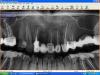

doktorenok Опубликовано 5 октября, 2011 Поделиться Опубликовано 5 октября, 2011 Ортопед принес снимок со словами, что нужно поставить имплант на месте 11. Я понимаю, что информации очень мало, только панорама, и я за такую работу, если и возьмусь, то очень не скоро, но все же какие возможны варианты реабилитации фронтального отдела? Выскажитесь пожалуйста все кому не лень. Я думаю, что однозначное удаление 12 и 21, пластика, а затем имплантация в позиции 12 и 21. Или вообще вариант имплантации здесь лучше не рассматривать? Ссылка на комментарий

Aldo Rain Опубликовано 5 октября, 2011 Поделиться Опубликовано 5 октября, 2011 мое мнение что имплантаты надо ставить в 12 и 22, делать как минимум мягкотканную пластику в области 11 Ссылка на комментарий

Kotyara Опубликовано 5 октября, 2011 Поделиться Опубликовано 5 октября, 2011 Ортопед принес снимок со словами, что нужно поставить имплант на месте 11. Я понимаю, что информации очень мало, только панорама, и я за такую работу, если и возьмусь, то очень не скоро, но все же какие возможны варианты реабилитации фронтального отдела? Выскажитесь пожалуйста все кому не лень. Я думаю, что однозначное удаление 12 и 21, пластика, а затем имплантация в позиции 12 и 21. Или вообще вариант имплантации здесь лучше не рассматривать? надо смотреть какая линия улыбки.Если низкая-то и не надо пластики, 2 винта как вы сказали и максимум-это розовая керамика.Но если средняя или не дай бог высокая, то без кост пластики ( только мягкими тканями вы тут не обойдетесь) ловить тут нечего. Будет проблема с временным протезом в таком случае Ссылка на комментарий

Ст@ся Опубликовано 5 октября, 2011 Поделиться Опубликовано 5 октября, 2011 чем 22 не угодил???+1По панораме невозможно оценить полный обЪем работ - навскидку - удаление 12, костная пластика, пластика слизистой (имплантация - м.б. с повторной пластикой.. Слишком мало исходных данных. Ссылка на комментарий

kriokov Опубликовано 5 октября, 2011 Поделиться Опубликовано 5 октября, 2011 чем 22 не угодил???в обл 22 похоже на гиперцементоз и деструкцию в сторону корня 23.имхо. Ссылка на комментарий